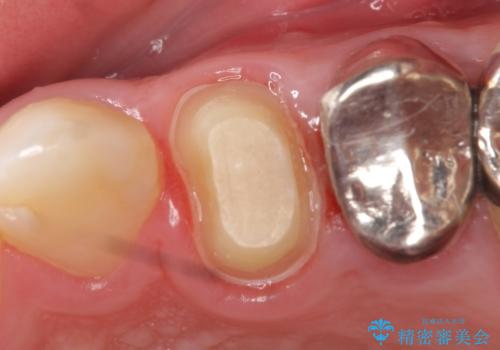

- 歯茎にできものが出来てなかなか治らないので診て欲しいといらっしゃった方の症例です。

診査の結果、左上4番目の歯の神経が死んでおり、根尖に膿が溜まっていることが原因とわかりました。

そのため左上4番目の歯は根管治療を行い、歯茎の膿の出口の消失を確認後、オールセラミッククラウンによる補綴を行いました。